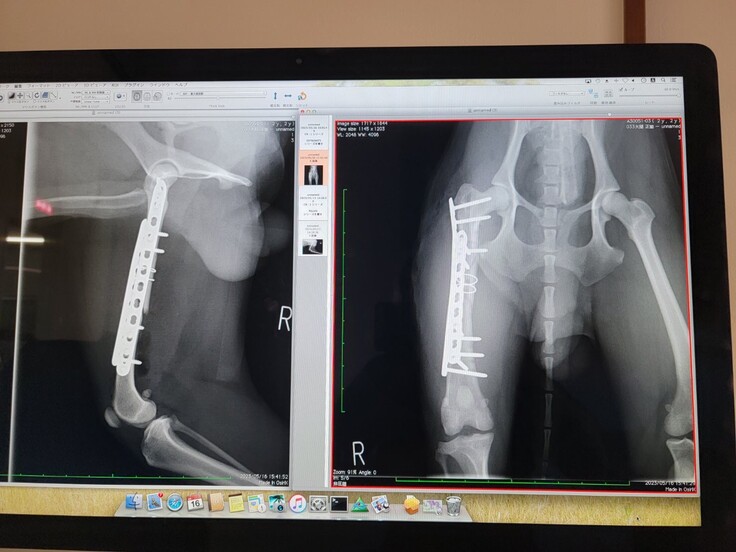

5月8日・病院でレントゲンを撮ってもらうと、右後脚大腿部が3か所複雑骨折をしていることが判明しました。かなり難しい手術になること、費用も高額になることの説明を受けました。

5月10日・この日の夜に緊急で手術してもらえることになりました。病院に連れて行くとき、ボランティアが抱きかかえると大きな悲鳴をあげました。それまでも痛かったろうに鳴いたこともなかったのに、、「ごめんね、絶対治してもらうからね、、」。かわいくてけなげなクルを乗せたボランティアの車が病院への道を急ぎます。医師からは、「複雑な折れ方をしているので、(骨に)ピンを入れて強化する施術ができず、プレートを添わせる方法をとる。手術後は絶対安静、1~2週間の入院になる」と説明を受けました。手術は5時間におよび、終わったのは翌10日の未明になりました。でもクルは頑張りました。ですが、予期せぬことが起こってしまいます、、、、、

5月14日・執刀してくださった獣医師と話ができ、翌日退院となりました。退院後は二週間ごとにレントゲンを撮って、再生具合を見ながらリハビリの運動開始、治療終了までは最低8か月くらいかかるであろうとの説明。それでも翌日退院です。私たちも安堵しました。ところがその夜獣医師から再び連絡があり、、・なんということでしょうか、骨折した足に埋め込んだプレートが折れ曲がってしまっていることが判明し、再手術となってしまったのです。

5月16日・再手術はより高度な設備が整った専門の病院で受けることに。最初の病院の獣医師の先生が、クルを自ら連れて行ってくださり、専門病院の先生と二人で執刀に当たってくださいました。先生方お二人による懸命の手術は無事に終了。クルは二度目の大手術も頑張りました。